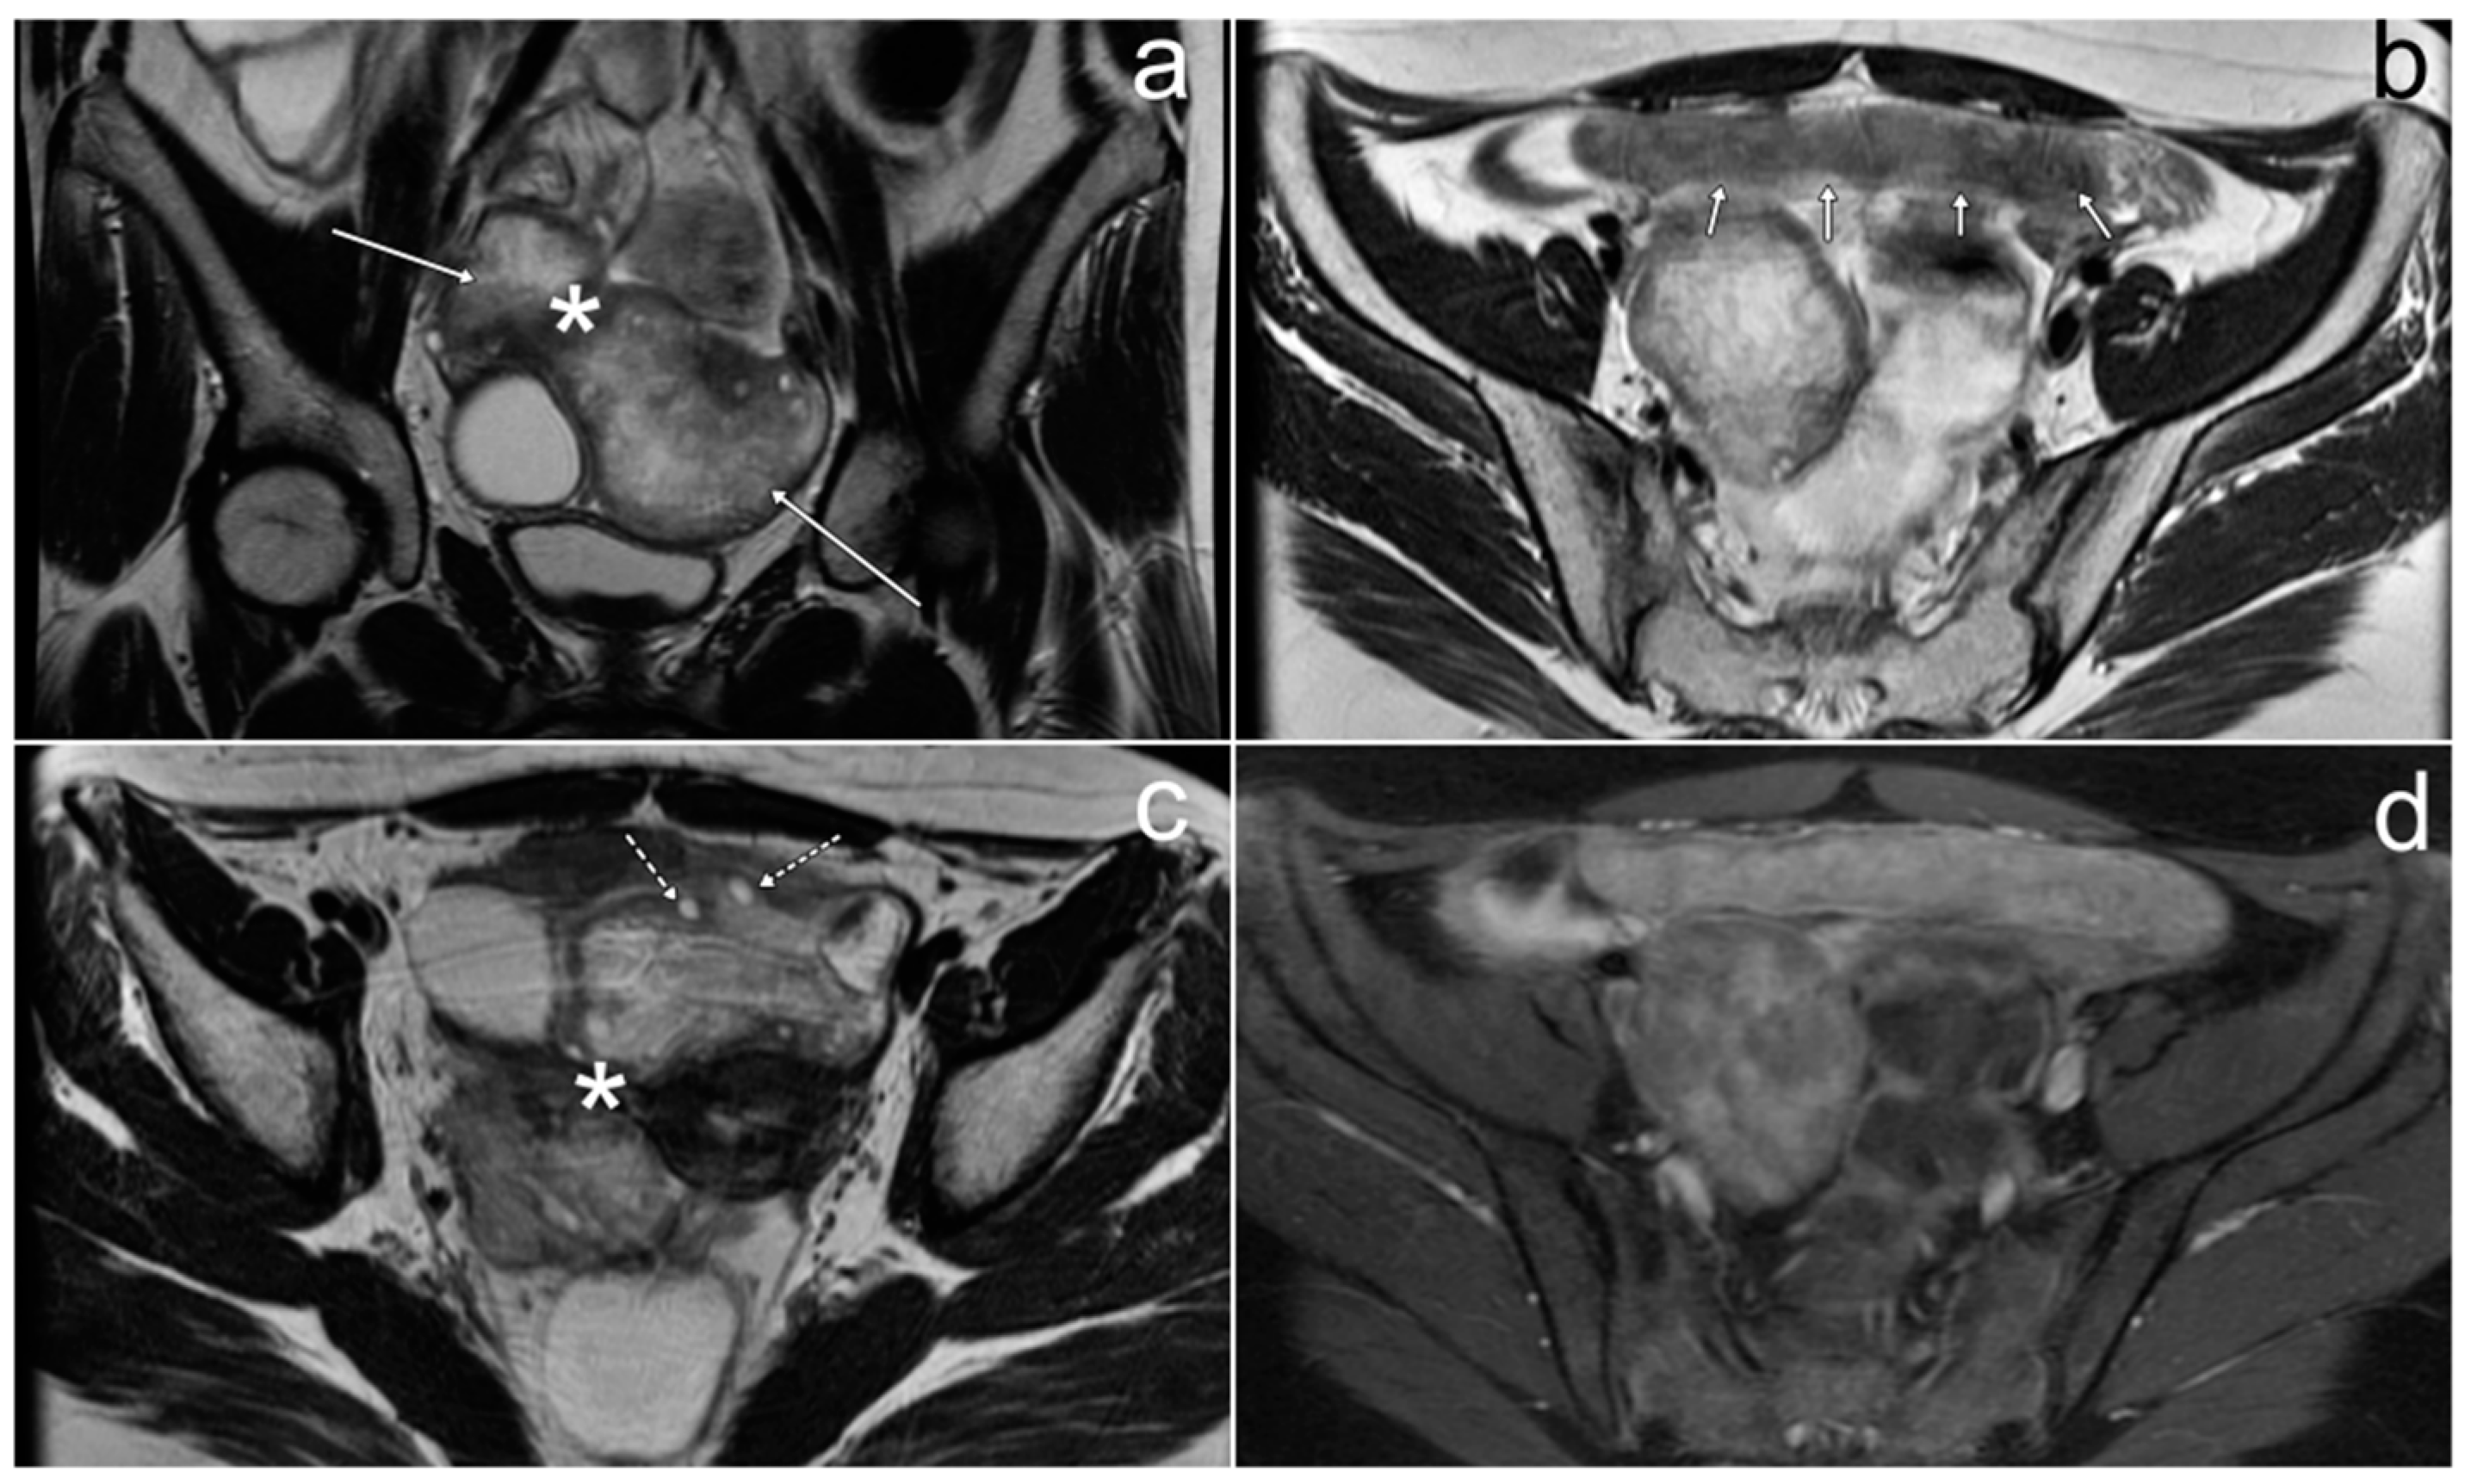

3.5. Primary Ovarian Angiosarcoma with Peritoneal Metastasis

Case Report

3.7. Pelvic Neuroblastoma

| Primary ovarian angiosarcoma | unilateral, sizable, cystic and solid elements in various proportions; hemorrhage; fibrous component | - | non-specific; asymptomatic or neurological symptoms, abdominal pain and distension |

| Neuroblastoma | heterogeneous mass due to calcification, hemorrhage, necrosis; strong diffusion restriction | - | asymptomatic palpable mass; urinary retention |